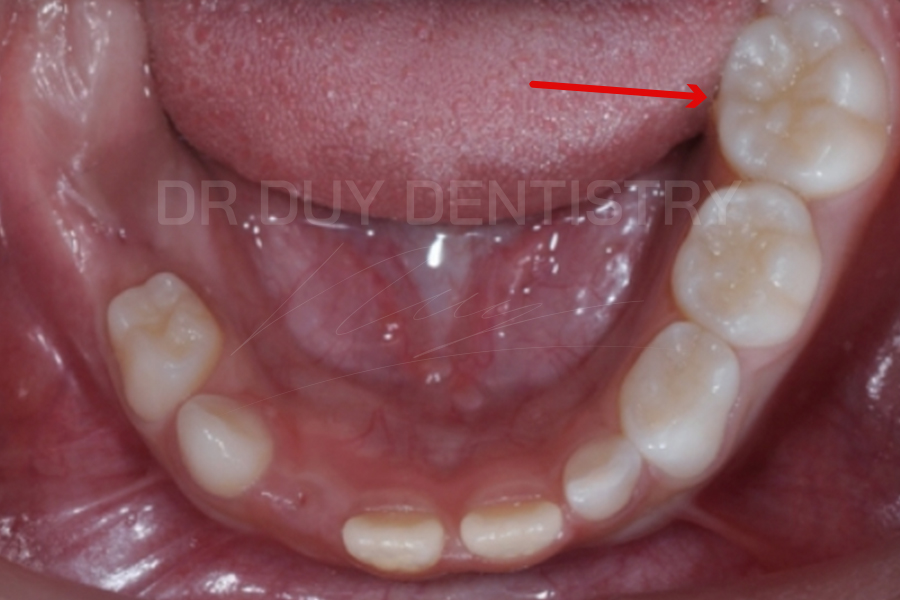

- Răng số 6 hay còn gọi là răng 6 tuổi, đây là chiếc răng cối lớn vĩnh viễn đầu tiên mọc lên khi trẻ 5-6 tuổi.

- Răng số 6 mọc lên ở vị trí phía sau răng cối sữa thứ 2 và không thay thế cho các răng sữa trước đó.

- Hay nói cách khác, chiếc răng này mọc thêm bên cạnh các răng sữa hiện tại của trẻ, do đó rất nhiều phụ huynh nghĩ rằng đây vẫn là răng sữa vì chưa thấy trẻ thay răng.